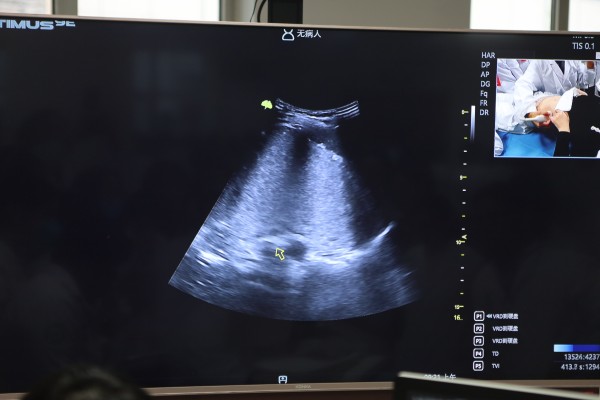

实操带教环节,辛集市中医院王震、邢台市第九医院钮世博、衡水哈励逊国际和平医院王文峰以及石家庄十二化建职工医院岳素宾作为指导专家在现场进行手把手实操教学,从胃到食管(部分)、从小肠到结肠再到阑尾,从实用解剖到手法切面,系统详尽地讲解让与会人员受益颇丰。为强化实操技能,培训班特别开展夜间练习模式,进行加餐训练。